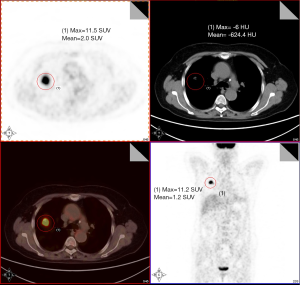

The study population consisted of 89 patients with CT-detected undetermined solitary pulmonary nodules (Figure 1). All the 89 subjects with clinical respiratory symptoms and CT signs suggestive of lung cancer were at high risk of developing cancer. Twenty-three healthy volunteers were also enrolled in the study. The control group matched well with disease group in age, gender, tobacco and so on. Informed consent was obtained according to guidelines from the fields of medical ethics and research ethics. This informed consent has been given based upon a clear appreciation and understanding of the facts, implications, and consequences of blood and tissue detection.